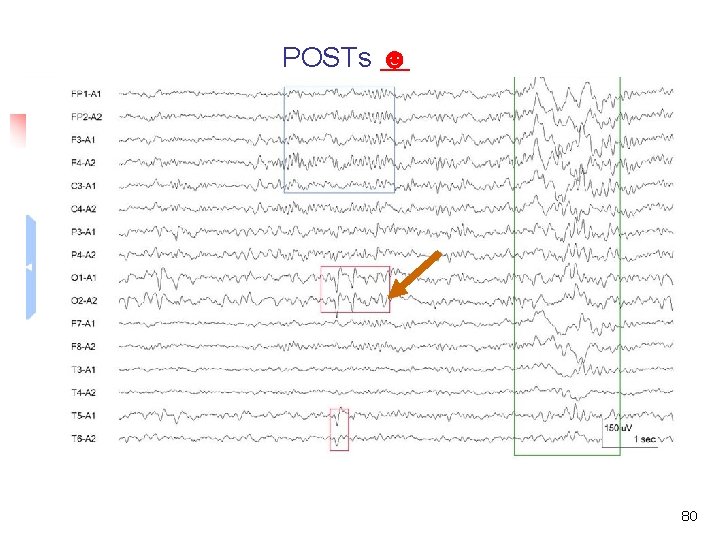

Normal sleep EEG of adults (over 20 yr) Elements of sleep EEG n Slow wave ☺ n Sleep spindles ☺ n Positive occipital sharp transients of sleep (POSTs) ☺ n Vertex sharp wave ☺ n K complexes ☺ Normal EEG in adult 43

Normal sleep EEG of adults (over 20 yr) Eye movements during sleep n Slow lateral eye movements ☺ n Rapid eye movement ☺ Normal EEG in adult 44

POSTs ☻ 80